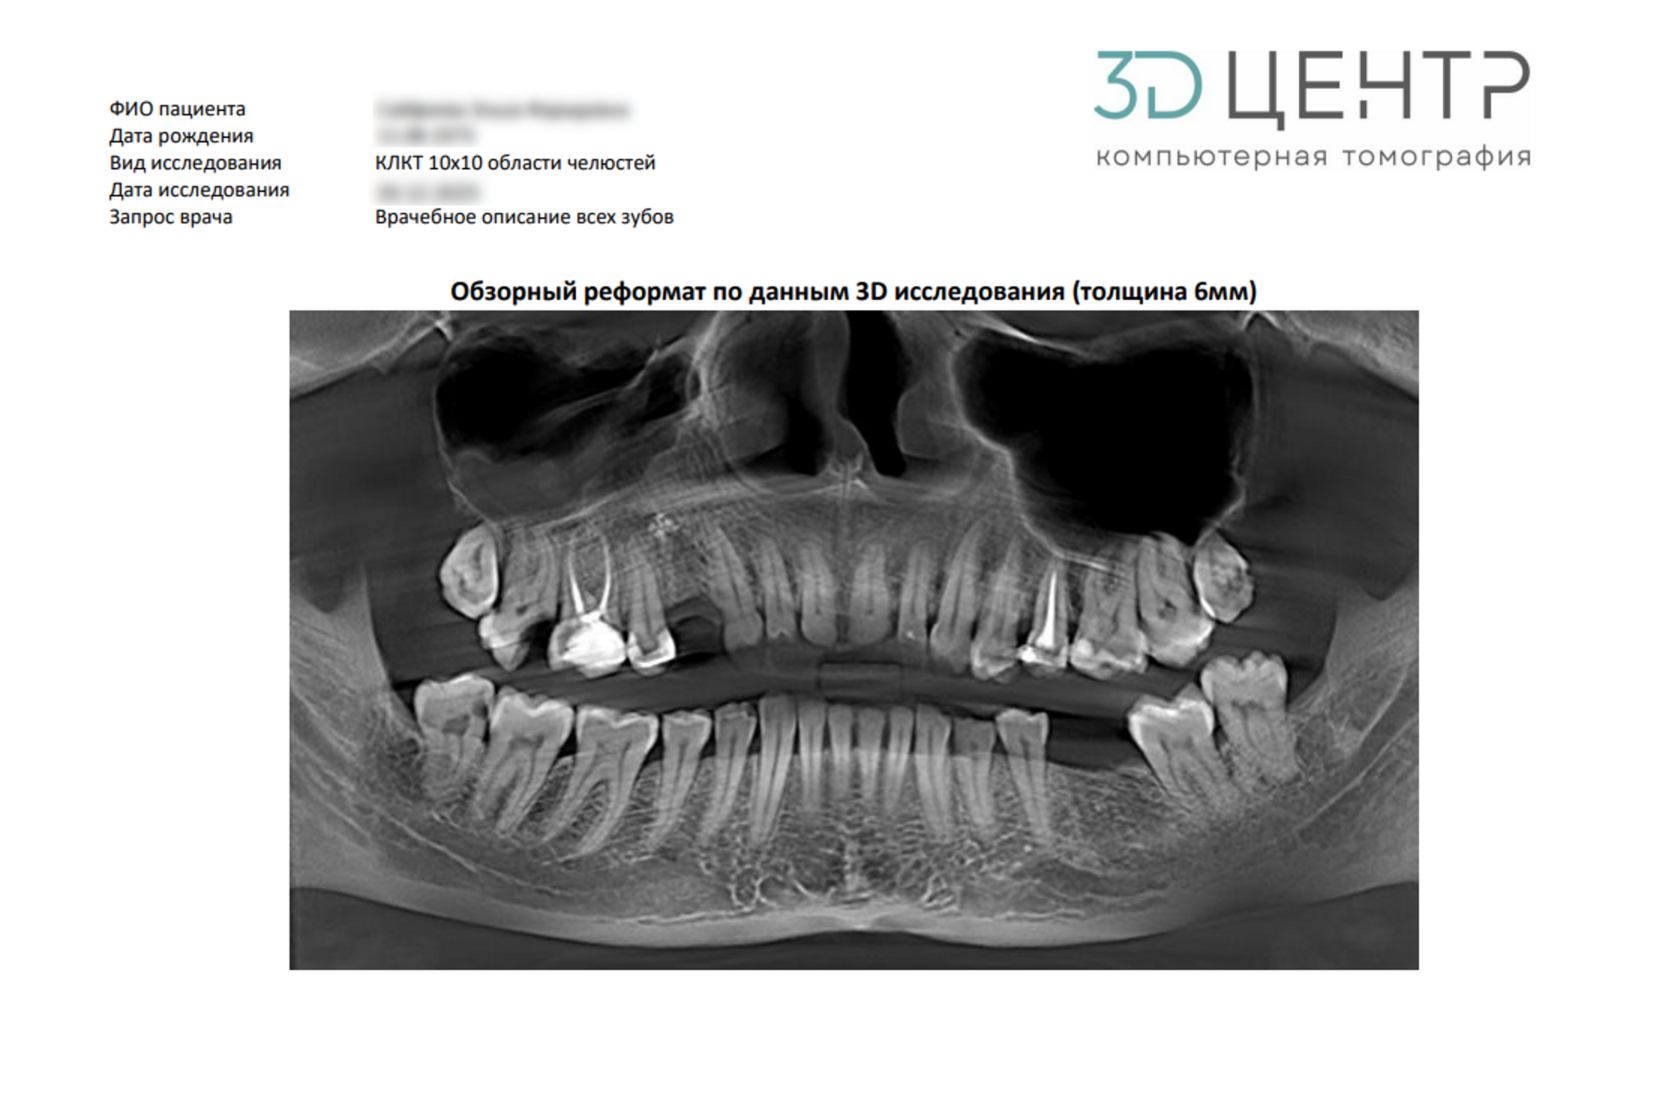

Планирование лечения с захватом нижней части гайморовых (верхнечелюстных) пазух, области третьих моляров - идеально для любых амбулаторных вмешательств.

Планирование имплантации, хирургических шаблонов и оценка ретенированных клыков.

Высокоточная эндодонтическая оценка, планирование одиночных имплантатов.

Скриншоты интересующей зоны\образования\группы зубов нижней или верхней дуги и ее описание.

Скриншоты интересующей зоны\образования\группы зубов (до 5 зубов) и ее описание.